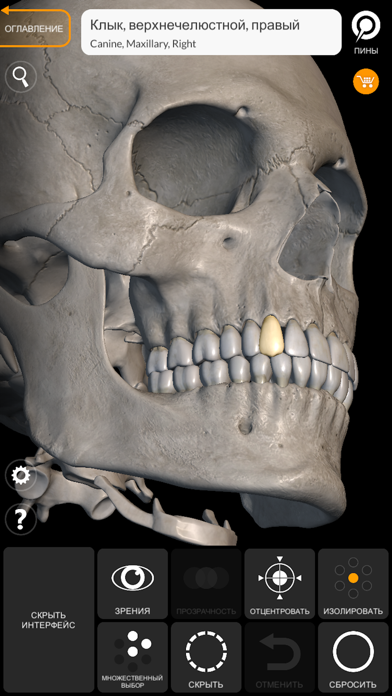

Скриншоты